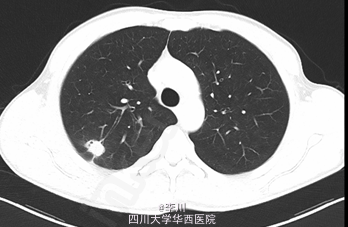

患者43岁男性,体检发现肺部阴影1+年,咳嗽1+月”。患者1+年前于成都军区总医院体检发现肺部异常阴影,当时患者无明显不适,定期随访无明显变化。1+月前,患者无明显诱因出现咳嗽,起初伴有咳少量白色泡沫状痰,自行服止咳药(具体药物及剂量不详)后症状无明显好转。遂复查胸部CT:

心肺腹查体无特殊异常。肺CT增强:右肺上叶软组织影,多系周围型肺癌伴胸膜牵拉,全身骨扫描:全身骨显像未见异常征象。头颅上腹部CT未见异常。

诊断为右肺上叶结节。有手术指征,遂在全麻下行VATS右肺上叶楔形切除活检+右肺上叶切除+淋巴结清扫+胸膜粘连烙断术。术中见: 结节均位于右肺上叶后段,约2.2cm*1.4cm大小,脏层胸膜皱缩、无侵犯壁层胸膜;术中冰冻结果:查见腺癌。手术顺利,术后予抗炎、化痰、对症等治疗。